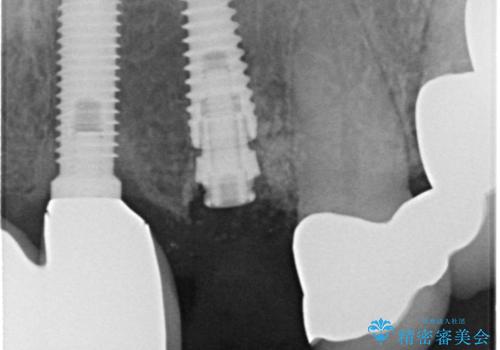

初回カウンセリング時にはセラミッククラウンが装着されていましたが、インプラント治療でのご来院時には前歯は外れて紛失をしてしまったとのことでした。

事前に仮歯の型取りをして用意をしていたため、インプラント埋入後に速やかに仮歯を装着しました。

インプラントの安定度も高く、抜歯と埋入から2か月後にはオールセラミッククラウンを装着することができました。